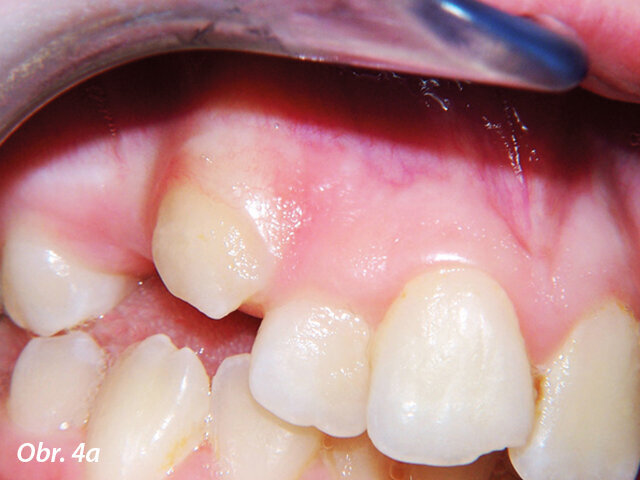

Hyperplazie gingivy před ošetřením.

Částečně prořezaný zub může často zpomalit průběh celé terapie. Recontouring dásní umožňuje správné umístění zámku a okamžité zahájení zařazování zubu ortodontickým aparátem. Nedostatečně prořezaný zub částečně krytý gingivou může být častěji postižen dekalcifikacemi, protože v průběhu terapie pacient není schopen vyčistit sklovinu v místě gingivální hyperplazie. Odvápnění v obtížně dostupných oblastech může ohrozit výsledky celé léčby. Po ukončení ortodontické terapie mohou být pro zlepšení estetiky laserem odstraněny zduřelé dásně, vždy však pouze v rámci biologických limitů (obr. 2–4).